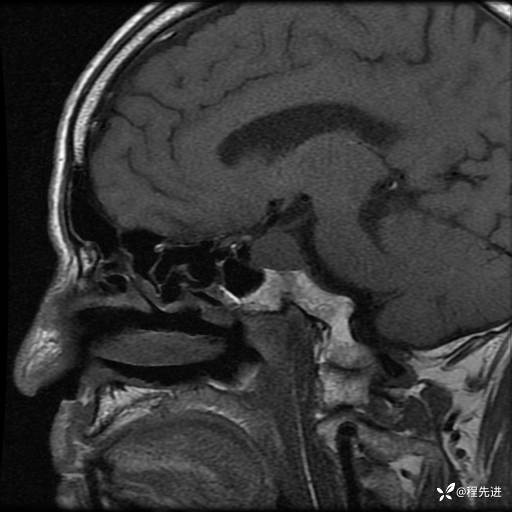

患者性别:男

患者年龄:74岁

简要病史:出现视物重影2月余,未予重视,2月来症状逐渐加重

MRI平扫+增强:

T1: